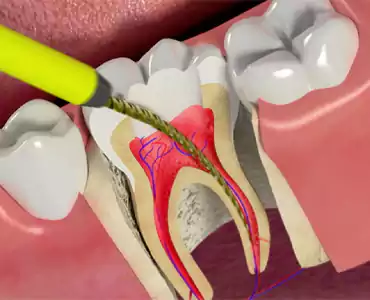

LATEST SERVICES

Our Services